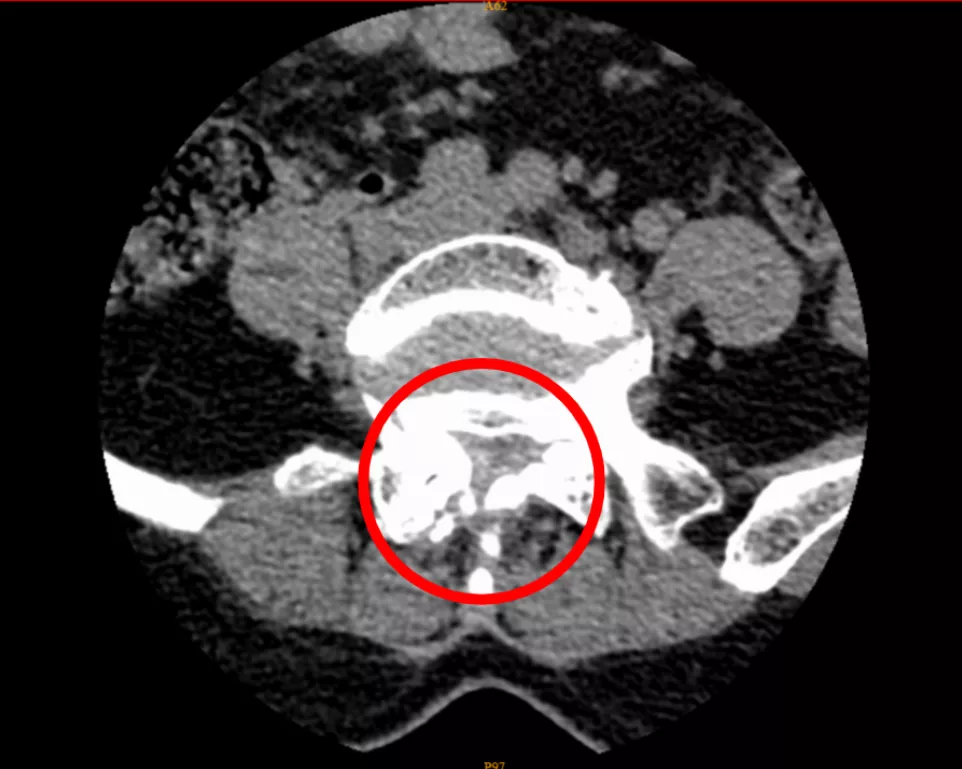

通过CT影像报告,疼痛科主任肖林发现了问题所在——腰椎管狭窄。

CT影像显示,李女士的腰椎管存在狭窄

肖林介绍,腰椎管是腰椎神经所在之处,腰椎神经支配着腰部及下肢关节,相当于城市中连接多个支干的主干道。腰椎管因髓核组织生长变狭窄后,便会压迫腰椎神经,使腰部产生强烈痛感,同时引起下肢疼痛。